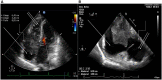

Figure 1

Baseline echocardiography of the patient from January 2020.